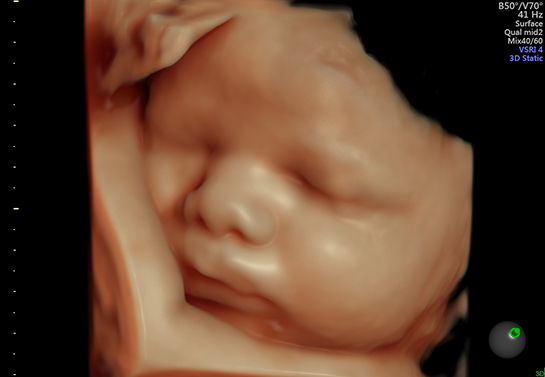

4D超音波検査について

4D超音波検査で赤ちゃんの立体的なお写真をとることができます。ご希望の方は、下記のとおりお申し込みください。

- 4D超音波に適した時期は妊娠16-30週頃です。

- 赤ちゃんの向きによっては、お顔がうまく映らないこともあります。(その場合には料金は頂きません。)

- 妊娠初期は赤ちゃんの全身の様子がよくわかりますが、お顔ははっきりしないことがあります。

- 妊娠24週頃からはお顔もはっきりしておなかもふっくらしてきます。

- 妊娠30週以降は赤ちゃんのお顔の表情がはっきりしてきますが、見えづらいことも多くなります。